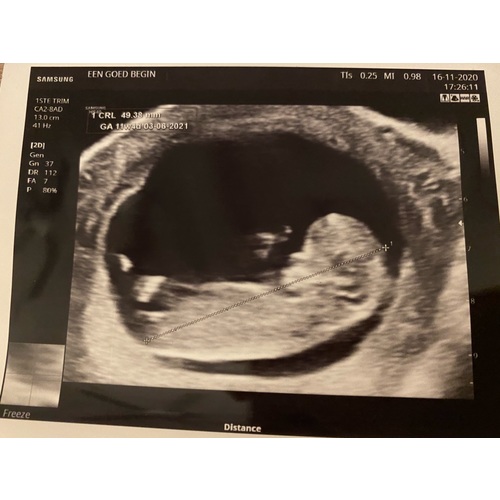

Vanmiddag de termijnen echo gehad, 19 oktober was ik 6 dagen terug gezet, vanmiddag bij de echo weer 6 dagen voorruit, de kleine deed het super, groeit goed en was een spring in het veld in de buik, heb een prachtig filmpje maar kan die niet plaatsen! Echt even een bevestiging van zwanger zijn! Ik heb 0.0 kwaaltjes dus maakte me toch wat zorgen dat het niet goed ging! Vandaag 11+4 wkn met de uitgerekende datum op 3 Juni 鉂も潳

Ahh, mooie echo!!! Ik had ook vandaag nu 11+1馃挄

Vandaag ook me 11 weken echo gehad馃挆馃挋 ...